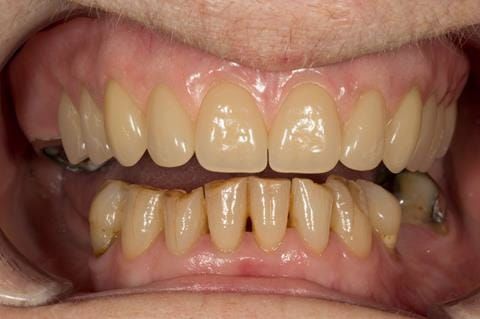

- Eight mandibular anterior teeth worn incisal edges from now extracted maxillary anterior crowns. Gingivitis - owing to inadequate oral hygiene.

Following consultation and second discussion appointment the patient chose to have option 2 namely, a window denture - maxillary cobalt chromium based partial denture. The clinical situation and treatment process is shown in detail below with photographs. The patient was successfully rehabilitated with this and her quality of life considerably improved. The clinical work was provided by Finlay and the technical work by Rowan.